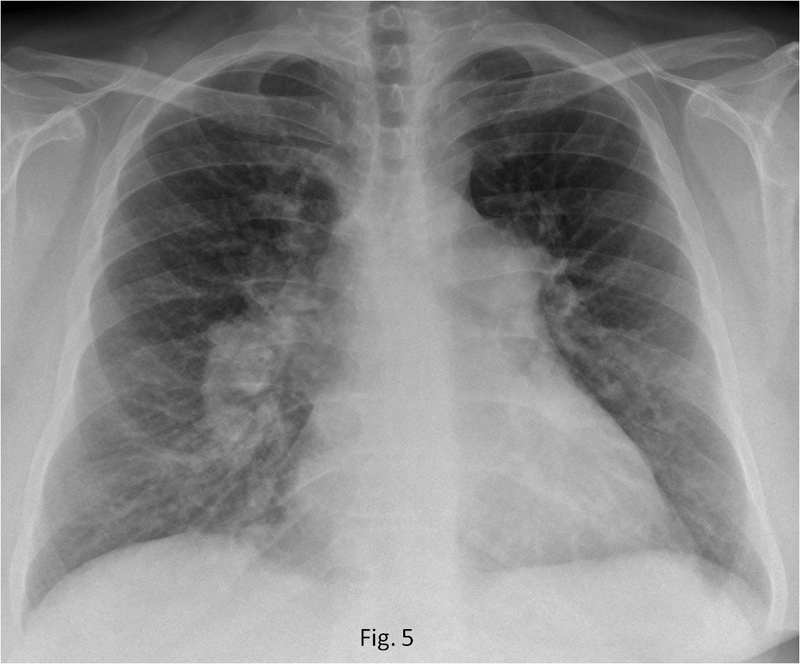

Tăng áp phổi là bệnh lý nghiêm trọng liên quan đến khả năng lưu thông máu trong động mạch. Bệnh lý xảy ra khi áp lực trong phổi tăng cao khiến cho tim phải làm việc nhiều hơn để máu đi qua phổi và lấy được oxy cung cấp cho cơ thể. Tình trạng này kéo dài sẽ khiến giảm lượng máu đến phổi và giảm lượng oxy trong máu. Việc tim hoạt động quá mức sẽ gây ra tình trạng suy tim phải và ảnh hưởng đến chức năng của các cơ quan khác trong cơ thể.

Do triệu chứng không điển hình và dễ nhầm lẫn với các bệnh lý khác nên tăng áp phổi thường không được phát hiện sớm làm giảm tỷ lệ sống sót ở người bệnh. Theo một số nghiên cứu, tỷ lệ bệnh nhân sống sót sau 5 năm điều trị là khoảng 50%. Tuy nhiên với sự tiến bộ của y học hiện đại, tỷ lệ tử vong của các bệnh nhân thấp hơn từ 20 đến 30% trong thời điểm từ 3 đến 5 năm.